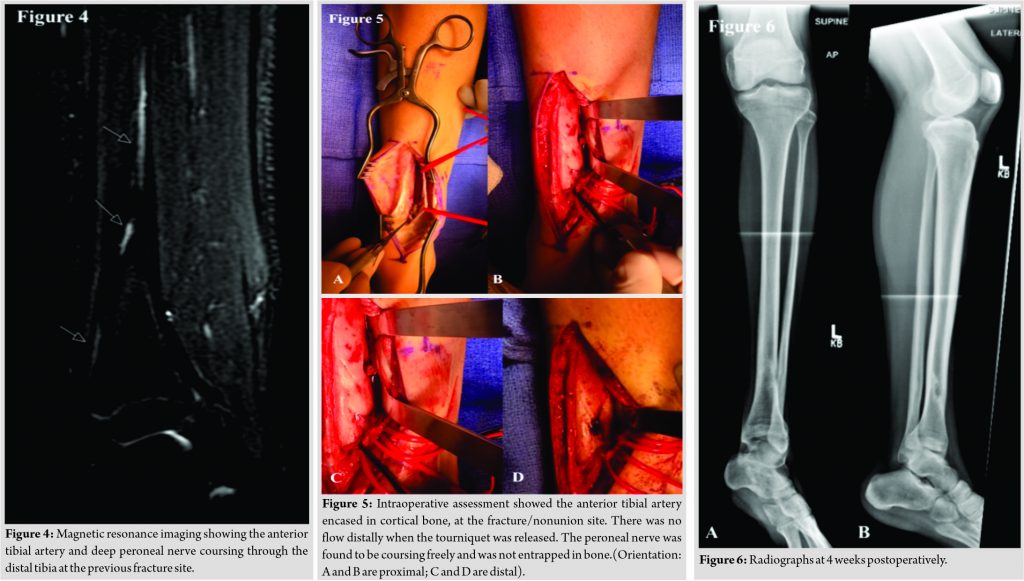

MRI demonstrated the anterior tibial artery and deep peroneal nerve embedded within the lateral distal tibial cortex (Fig. 4). Given the patient’s persistent pain at the fracture site and concern for entrapment of the neurovascular bundle in the setting of partial nonunion, surgical intervention was offered. The decision was made to proceed with exploration and removal of the neurovascular bundle from within the cortical bone. We discussed that if the artery appeared to be coursing through the bone, it would likely not be functional. Given his foot remained well perfused, bypass was not planned (even if the anterior tibial artery was nonfunctional). A longitudinal incision was made along the distal third of the anterior tibial crest of the left leg. Sharp dissection was carried down through the floor of the anterior tibialis tendon sheath. The periosteum was elevated using a Cobb elevator, to expose the anterior tibial artery and deep peroneal nerve. Exploration of the deep peroneal nerve showed it to be adherent to the periosteum, but not encased within the bone. The nerve was mobilized and neurolyzed throughout the entire zone of injury. The nerve was protected for the remainder of the procedure. The anterior tibial artery was encased in bone, entering the tibial cortex approximately 9 cm above the tibiotalar joint and exiting approximately 4 cm above the tibiotalar joint (Fig. 5).

An osteotome was used to create a trough in the tibia, extending from the entrance and exit points of the anterior tibial artery. The artery was easily removed from the bone after creation of the trough and was left in continuity. The artery was found to be non-pulsatile when the tourniquet was released. The patient was placed in a soft dressing and allowed to weight bear as tolerated in a walking boot. The post-operative course was uncomplicated. The patient was seen at 6 weeks postoperatively. He reported significant improvement in his pain compared to preoperatively. He had been wearing the boot while out of the house. He had not yet returned to sporting activities. Examination at that time showed no motor or sensory deficits and a normal vascular exam. Radiographs showed the cortical defect along the lateral distal tibia with signs of ongoing healing at the fracture site (Fig. 6). The patient was allowed to gradually return to his activities. He will be seen again at 6 months postoperatively.